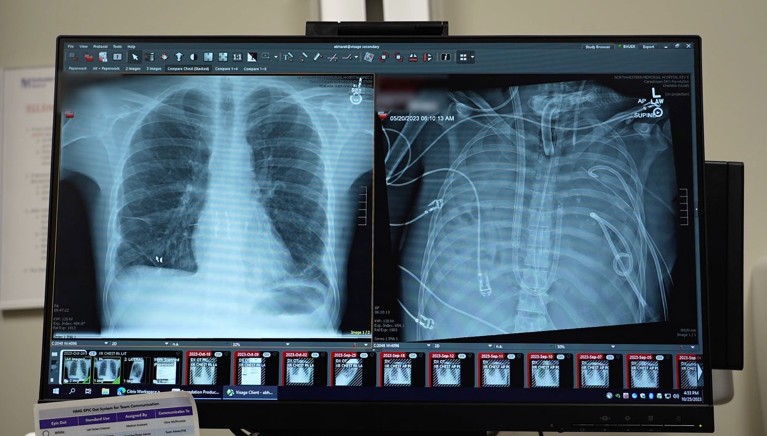

A 33-year-old man survived for 48 hours after surgeons removed his infected lungs and connected him to an external artificial-lung system developed by a team led by thoracic surgeon Ankit Bharat at Northwestern University. The device is notable because it maintains a balanced, continuous flow of blood through the heart while oxygenating blood — unlike previous extracorporeal devices that cannot preserve normal cardiac flow.

The patient had acute respiratory distress syndrome after influenza, then a drug-resistant Pseudomonas aeruginosa infection that caused septic shock and organ failure. After lung removal and support on the artificial-lung system, his blood pressure support was weaned, kidney function recovered and his heart function normalised within 48 hours. He then received a double lung transplant and, almost three years on, shows no signs of rejection or impaired lung function. The results were published in Med.

The man developed ARDS from influenza, was ventilated, then acquired a drug-resistant Pseudomonas infection that led to pus-filled lungs, septic shock and multi-organ failure. He arrested and was dying, so clinicians elected to remove the infected lungs. The novel external artificial-lung system kept him oxygenated and maintained cardiac blood flow, enabling rapid physiological recovery and a successful double lung transplant shortly afterwards.